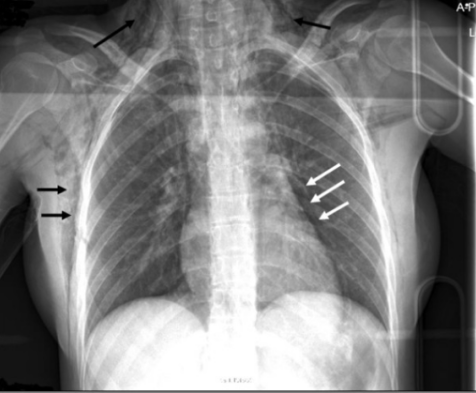

溶骨所見:下写真の矢印部位。胸部レントゲンで一緒に写る上腕骨で溶骨所見が見られることもある。溶骨性の骨転移がうつりこんでることがあるのでよくチェック。

骨折はないか:肋骨をひとつひとつ見ていく。黒矢印のところで肋骨骨折が見られる。

皮下気腫がないか:下図の黒矢印が皮下気腫の所見。白矢印は縦隔気腫。

X-ray of chest on day of injury. Black arrows: subcutan | Open-i